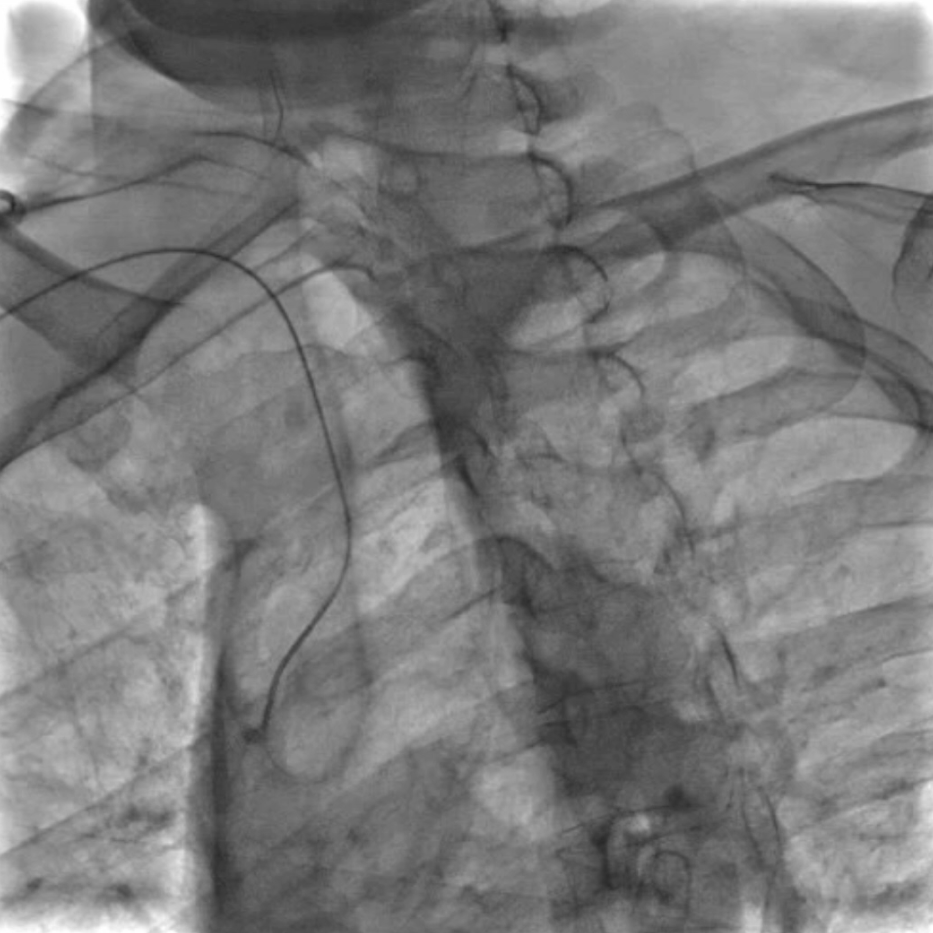

穿刺与鞘管置入:局麻下穿刺右侧桡动脉,置入6F动脉鞘;

导管塑形与定位:使用SIMMONS导管选择左侧颈总动脉,操作时需轻柔(避免导管头端触碰血管壁导致斑块脱落),通过“反八字”塑形可精准对接左侧颈总动脉,导管弯部挂于颈动脉分叉处提供稳定支撑;

长鞘置入:在左前斜位透视下送入90cm长鞘,全程观察方向以避免阻力过大导致血管损伤